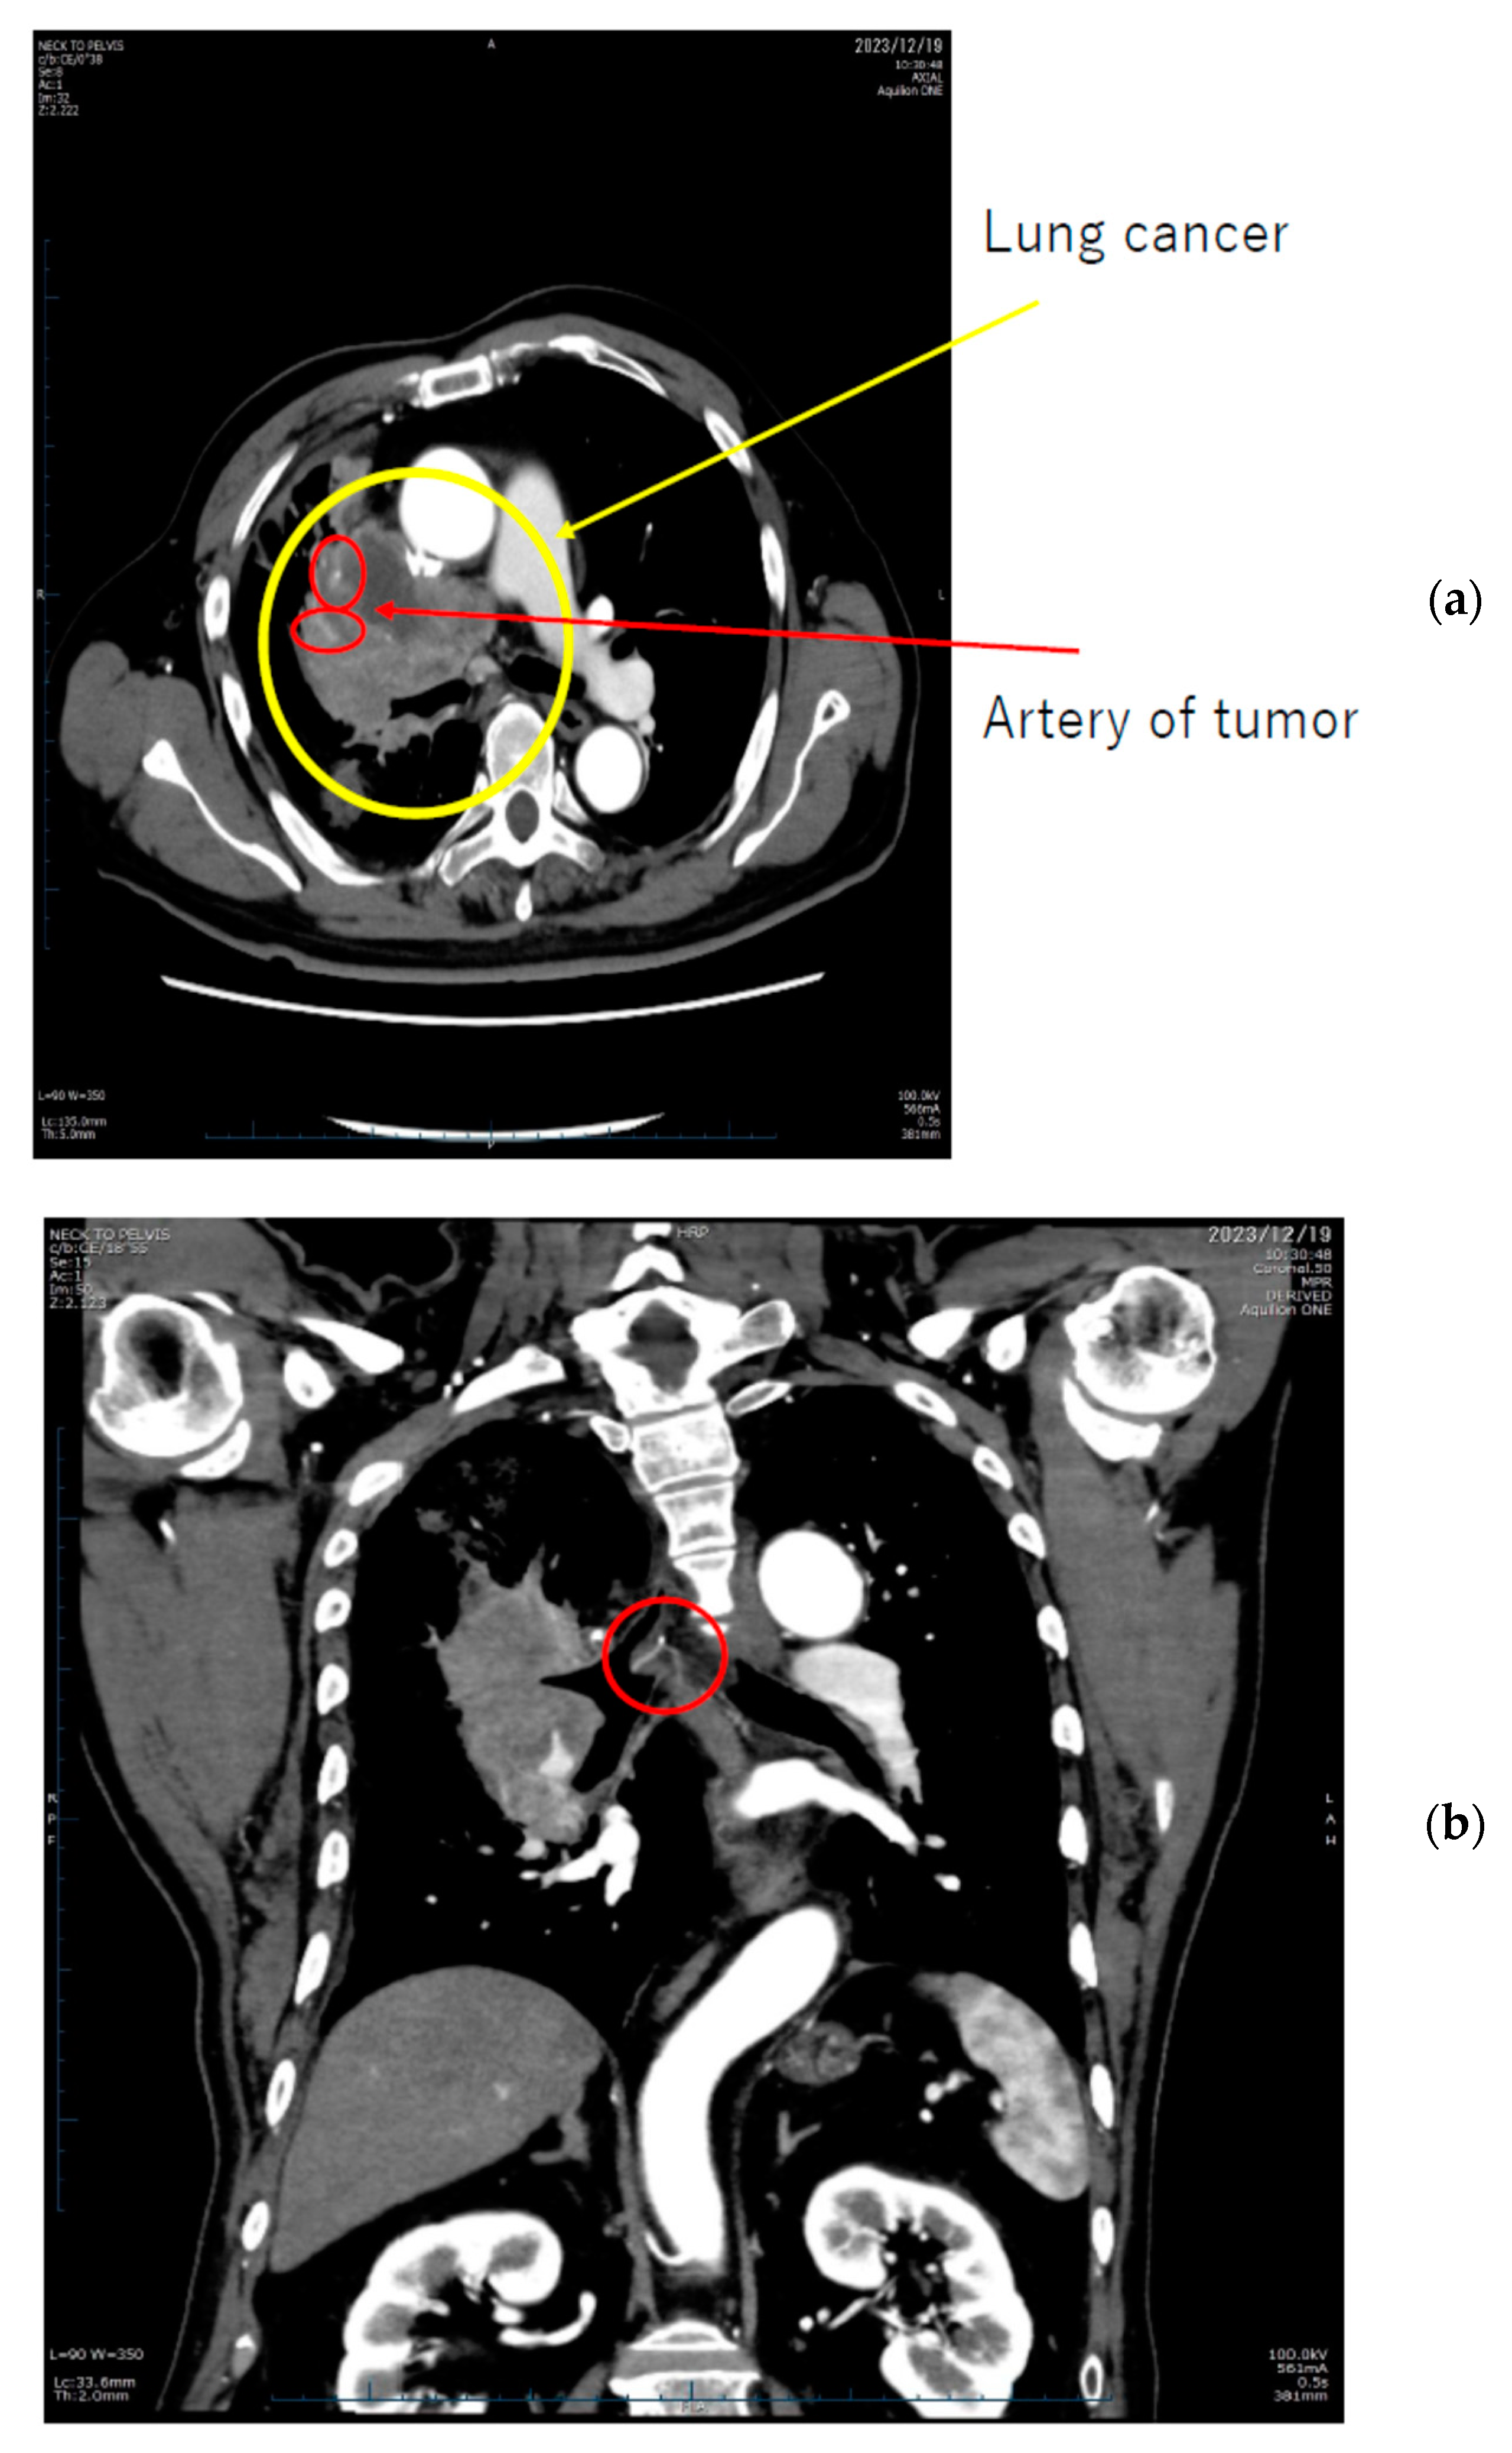

Additionally, Figure 6 delineates the locations of extravasation detected in a patient’s lung cancer as visualized on CT images. Specifically, in panel (b), one of the feeding arteries of the tumor (the right bronchial arterial) is depicted. Identifying the responsible vessel on CT proved challenging, leading to the decision to embolize this artery. The patient had previously experienced hemoptysis prior to initiating chemotherapy.

Figure 6.

Lung cancer extravasation sites highlighted with circles in (a,b).